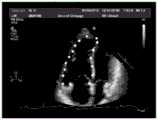

FIG. 8 is a schematic illustration of labeling the identification result of the cardiac anatomical structure provided by the embodiment of the present application;

Then, for the apex, base, and tricuspid rings, the positions thereof are determined by performing pixel position weighted average processing based on the pixel values. For the endocardium and ventricular septa, binarization and skeleton extraction processing are performed on the probability thermodynamic diagrams to obtain the position labels as shown in fig. 7.

Finally, the positions of the various anatomical structures can be marked in the original ultrasound image of the heart, based on the determined location indications of the apex, base, tricuspid annulus, endocardium and ventricular septum, for example as shown in fig. 8.

As can be seen from comparing fig. 8 and fig. 5, the result of identifying the anatomical structure in the cardiac ultrasound image by using the technical solution of the embodiment of the present application is substantially consistent with the position of the anatomical structure labeled in advance, that is, the technical solution of the embodiment of the present application can accurately identify the anatomical structure in the cardiac ultrasound image.